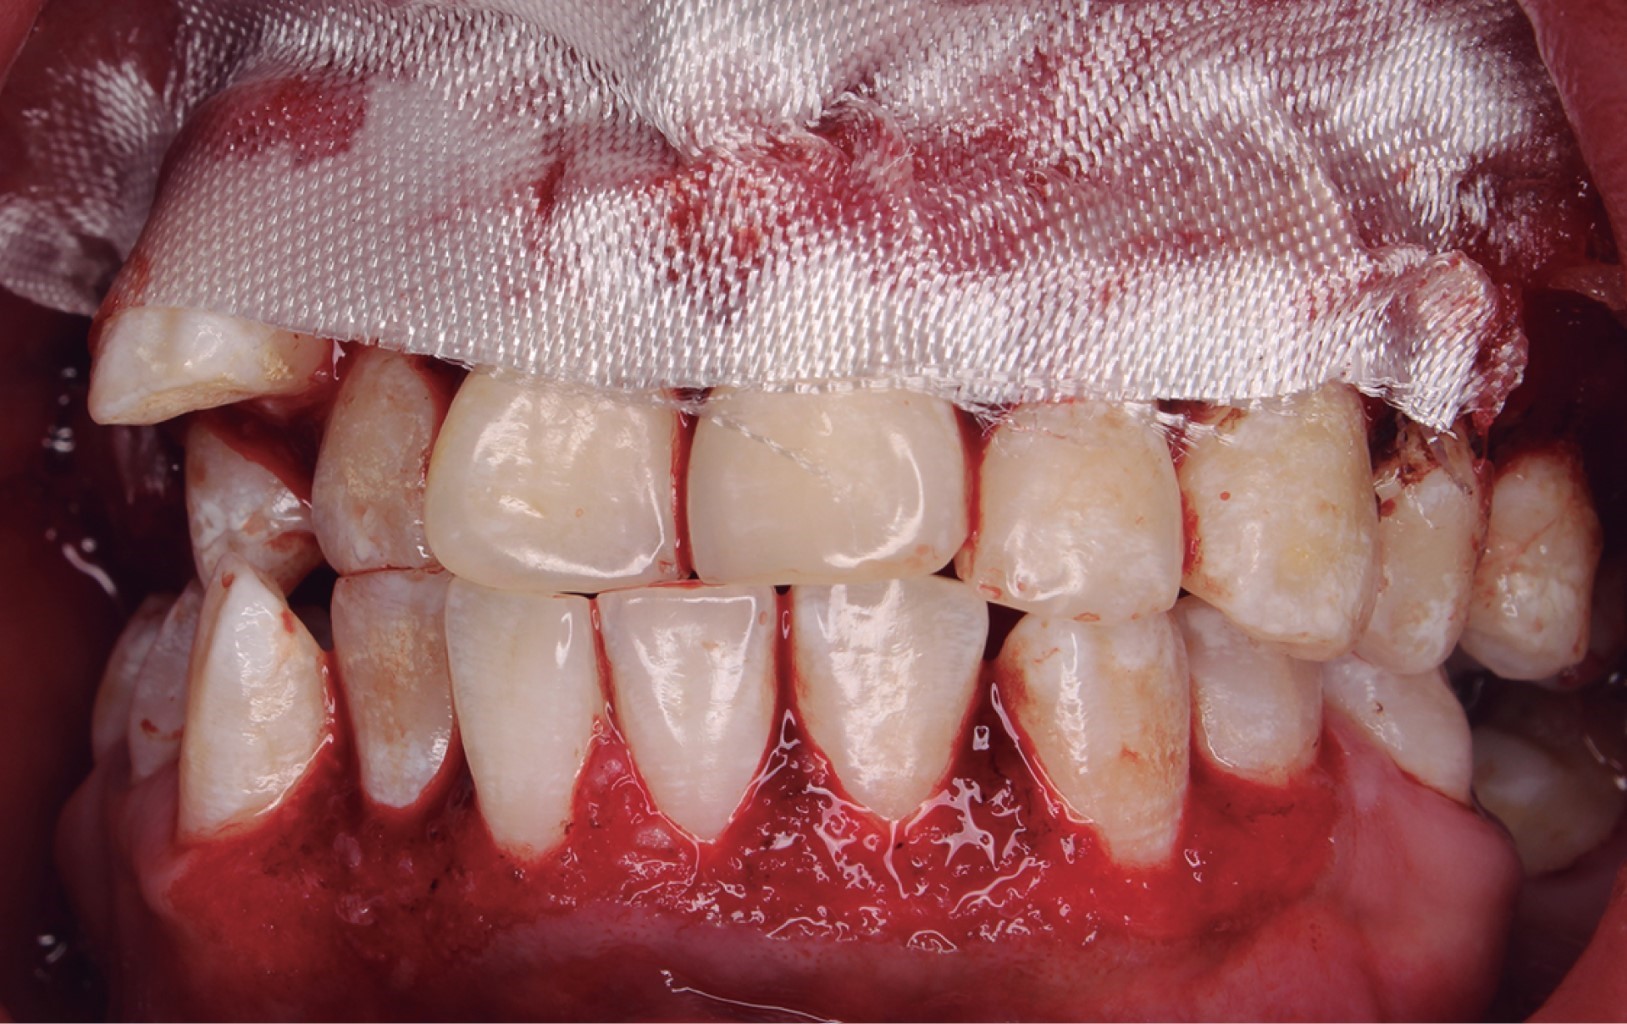

Al realizar el examen clínico se observó presencia generalizada de placa dentobacteriana y malposición dental, aumento de volumen en la encía en las caras vestibulares y palatinas del sextante #2, y en la cara vestibular del sextante #5 de color rosa pálido con márgenes eritematosos y nodulares cubriendo un tercio de la corona clínica, al momento de sondear hubo presencia de sangrado (Figura 1).

Figura 1